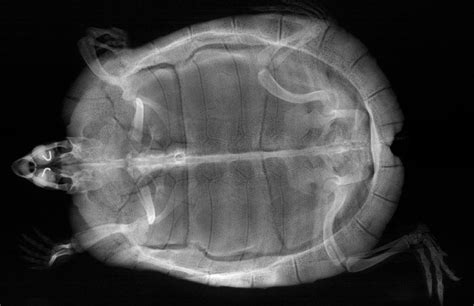

So, what exactly can a PSEi Turtle X-ray show you? The answer is quite a lot! This diagnostic tool is incredibly versatile, providing detailed information about a turtle’s internal structures. One of the most common uses of X-rays is to identify bone fractures. Turtles, with their hard shells, may seem well-protected, but they are still susceptible to injuries. Accidents, falls, or even rough handling can lead to shell fractures, and X-rays are the only way to accurately assess the extent of the damage. An X-ray can show the location, severity, and type of fracture, guiding the veterinarian in determining the best course of treatment. Another significant application is the detection of internal organ problems. X-rays can reveal the presence of tumors, abscesses, or other abnormalities in the lungs, heart, liver, and other vital organs. These issues are often difficult to detect through a physical examination, making X-rays essential for early diagnosis and treatment. In addition, X-rays can be used to identify foreign objects that a turtle may have ingested. Turtles are known to be curious eaters, and they may accidentally swallow small objects like rocks, plastic pieces, or even small toys. An X-ray can quickly pinpoint the location of the object, allowing the vet to determine whether it needs to be removed surgically or if it can be passed naturally. Furthermore, X-rays can also provide valuable information about the overall health of a turtle. For example, they can assess the density of the bones, which is an indicator of the turtle’s nutritional status and overall health. They can also show the size and shape of the internal organs, which can provide insights into potential health problems. By carefully examining the X-ray images, veterinarians can gain a comprehensive understanding of a turtle’s internal condition, allowing them to make accurate diagnoses and develop effective treatment plans. This detailed information is critical for ensuring the health and well-being of these fascinating creatures.

So, the PSEi Turtle X-ray is ready, and you’re curious to see what it reveals. While you might not be able to interpret the images like a veterinarian, understanding a few key things can help you better understand your turtle’s health. First, you’ll want to focus on the skeletal structure. Look closely at the bones, paying attention to their shape, density, and any signs of damage. Healthy bones will appear solid and well-defined, while fractures or other abnormalities will be clearly visible. Next, examine the internal organs. The vet will be looking for the size, shape, and position of the organs. For example, the lungs should appear clear and free of any fluid or masses. The heart should be the correct size and shape, and the liver and other organs should appear normal. If there are any irregularities, it could indicate a problem that requires further investigation. Finally, pay attention to any foreign objects that might be present. These could include swallowed rocks, pieces of plastic, or other materials. The vet will be able to pinpoint the location of the foreign object and determine whether it needs to be removed. Remember, X-rays provide a snapshot of your turtle’s internal condition. They are a valuable diagnostic tool, but they are just one piece of the puzzle. The vet will also consider the turtle’s medical history, physical examination findings, and other diagnostic tests when making a diagnosis. By combining all of this information, the vet can create a comprehensive picture of your turtle’s health and develop the best possible treatment plan. The images are a tool to identify the right treatment plan.